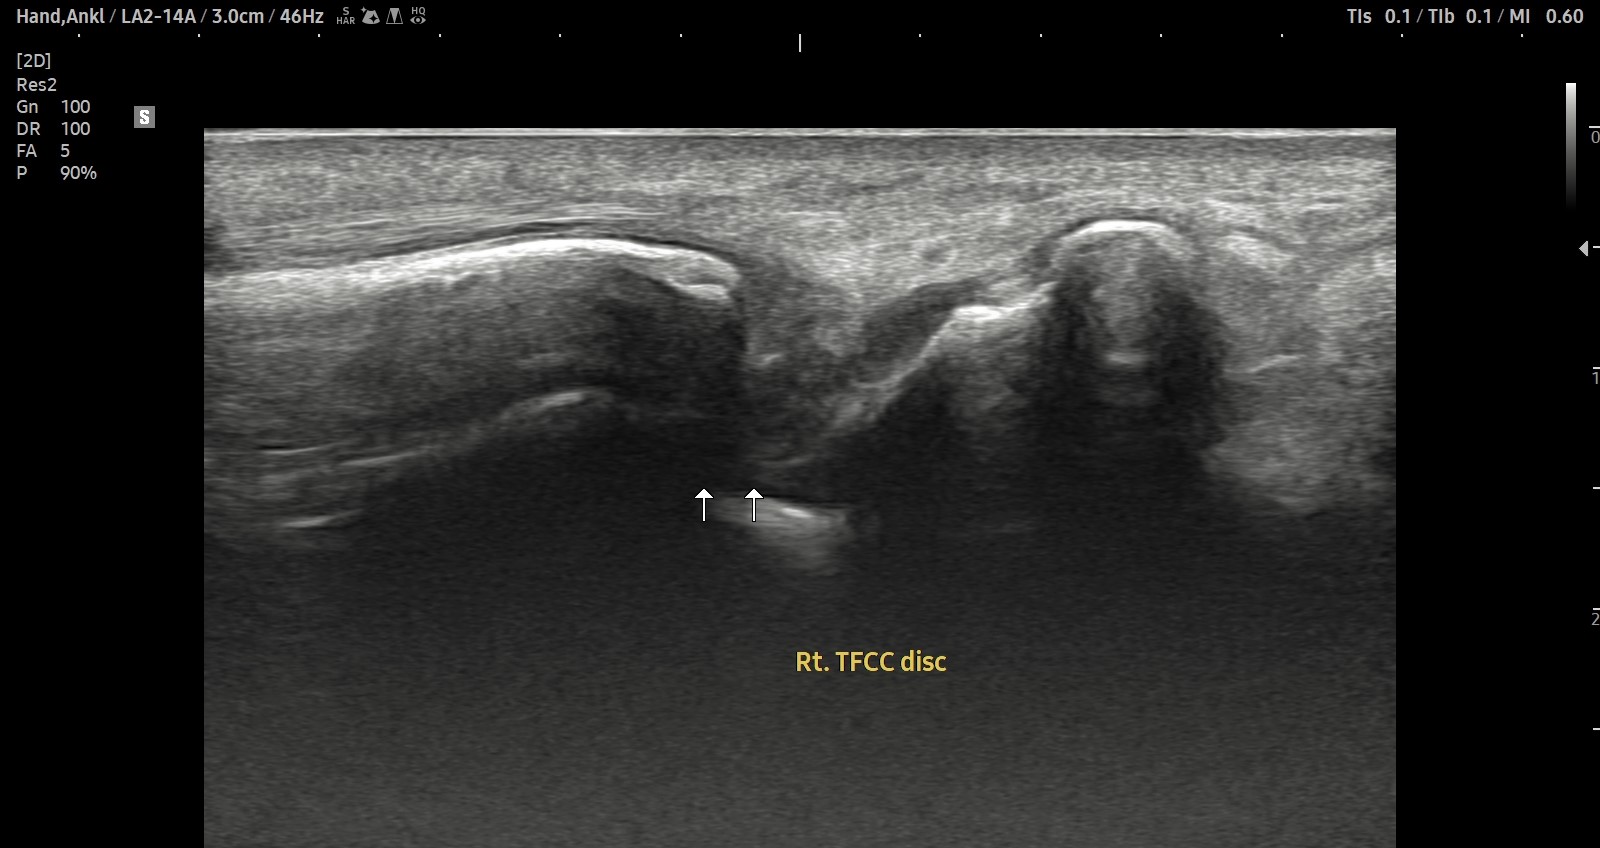

치료 후기에 사용된 전/후 검사 사진은 동일 인물의 결과이며 각 지점 동일 조건에서 촬영되었습니다.

개인에 따라 치료 결과에 차이가 있을 수 있으며, 부작용이 발생할 수 있습니다. 내원 후 충분한 상담을 받으시고 치료를 진행하시면 됩니다.

- 치료기간 : 25 .5 30 . ~ 25 . 6 .27

- 치료횟수 : 5 회(dna 1cycle)